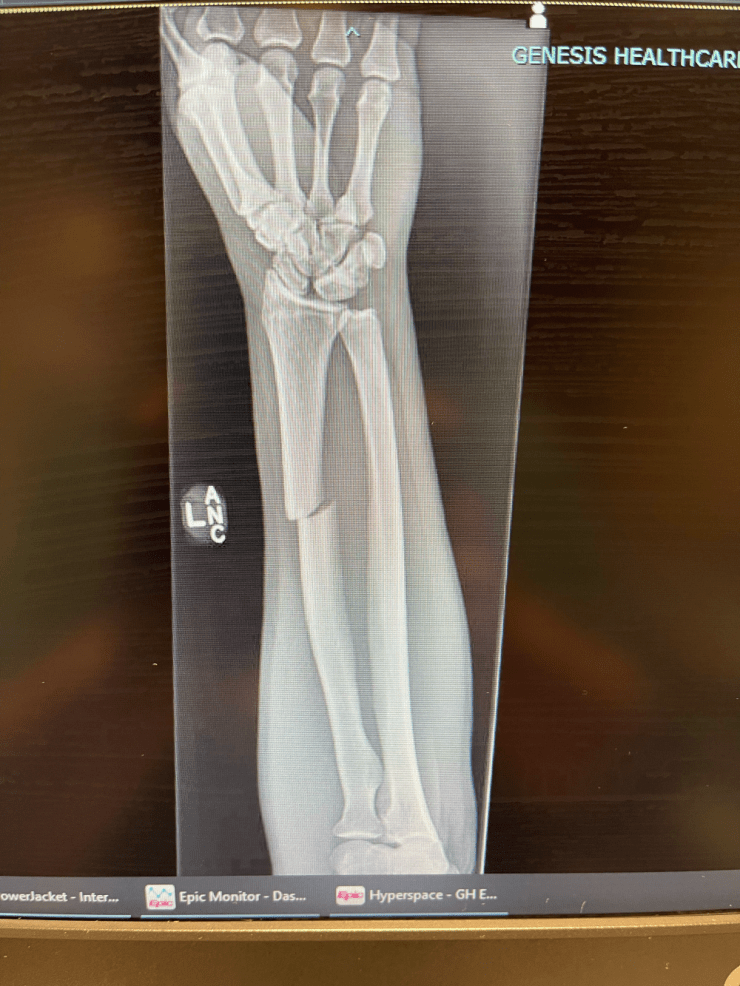

Writing is slow and difficult so posts will be short for a while. The crash was on October 23 and surgery on the 29th. So now just a clumsy ass cast that gets in the way and annoys me, but just a moment in time.